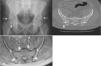

Bone fusions in the cervical spine, calcification of ligaments and syndesmophytes in the lumbar spine were observed through spine radiography (Figure 1), and Grade II (right)/Grade III (left) sacroiliitis was observed through sacroiliac joint radiography. Computed tomography (CT) revealed ankylosis foci at the sacroiliac joint (SI) and bilateral ossification of the iliolumbar ligament (Figure 2B). Similarly, magnetic resonance imaging demonstrated ossification of the iliosacral ligaments in the lower portions of the sacroiliac joints and no significant findings in the upper portions of the SI joint (Figure 2C).

A- Hip radiograph showing bilateral ossification at the superior acetabular margin (arrows). B- Pelvis CT showing foci of ankylosis in the lower portion of the sacroiliac joint (arrows). C- Axial fat sat T2-weighted turbo spin-echo showing the lower portion of the sacroiliac joint with ossification of the iliosacral ligaments (large arrows). There are no significant findings in the upper portions of the sacroiliac joint (small arrows).